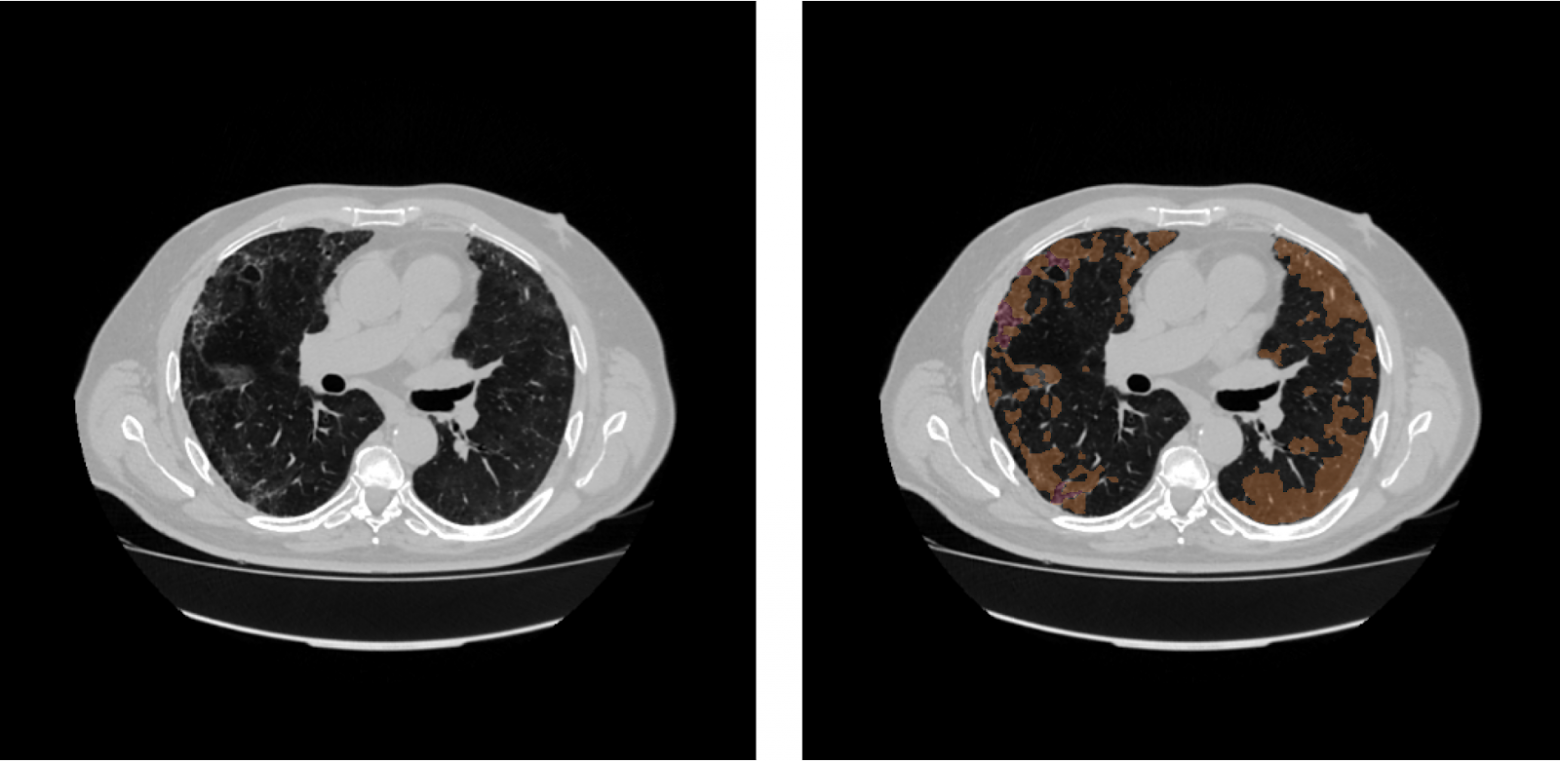

Как обучить нейросеть, если разметка данных стоит как самолет

Искусственный интеллект все чаще используется в медицинских целях, в частности для анализа медицинских изображений. Это прекрасный помощник для врачей-рентгенологов, который позволяет определять даже едва различимые человеческому глазу признаки патологий и вообще разгружает медицинских специалистов за счет автоматизации ряда рутинных задач.